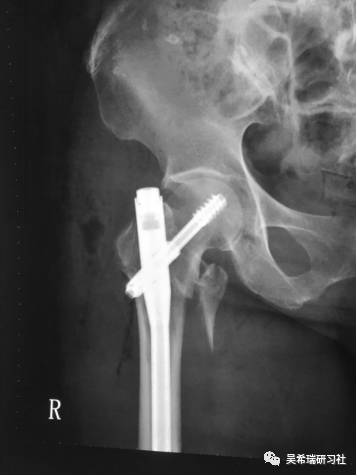

病例2

髓内钉固定后1.5年迟发性低度感染取出髓内钉清理髓腔自制骨水泥髓内钉占位器15天愈合

TIPS:清理髓腔是关键全髓腔感染可以用扩髓器占位器15天左右取出,时间久成为异物全身应用敏感抗生素